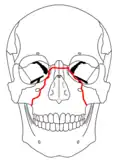

| Fraturas 3 de Le Fort | |

No início do século XX, René Le Fort mapeou as regiões faciais típicas dos traumas maxilo faciais, agora conhecidos como Fraturas I, II, e III de Le Fort (direita).[11] A Fratura I de Le Fort, também chamada de Fratura de Guérin ou Fratura transversa,[12] envolve a maxila, separando-a do palatino.[13] A Fratura II de Le Fort, conhecida também como Fratura piramidal,[12] atravessa os ossos nasais e o aro orbital.[13] A Fratura III de Le Fort, por sua vez, chamada também de Disjunção crâniofacial,[12] atravessa a frente da maxila e envolve as suturas zigomaticofrontal, maxilofrontal nasofrontal, os assoalhos das órbitas, a etmóide e o esfenóide.[12] As Fraturas de Le Fort, responsáveis por 10-20% das fraturas faciais, são frequentemente associadas com outros ferimentos graves.[13] Le Fort fez seu trabalho com base em cadáveres e caveiras, e o sistema de classificação tem sido criticado como impreciso e simplista uma vez que a maioria das fraturas de meia-face envolvem uma combinação das fraturas de Le Fort.[13] Embora a maioria das fraturas faciais não seguem os padrões descritos por Le Fort, seu sistema ainda é utilizado para categorizar os diversos tipos de traumatismos.[14] http://www.angelfire.com/nm/cirurgia/pritra/Image90.gif